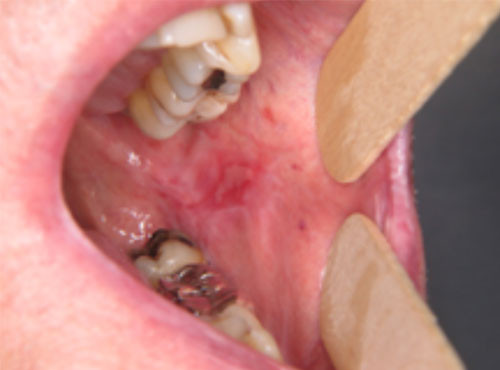

Examen clinique. On observait une ulcération jugale gauche bordée par un érythème et un réseau kératosique blanchâtre. La lésion était située en regard de restaurations dentaires à l’amalgame et d’une couronne métallique. L’examen de la joue droite montrait un réseau kératosique et la langue présentait des plaques kératosiques. La palpation de la muqueuse en regard des lésions ne retrouvait aucune induration.

Examen paraclinique. Une biopsie a été réalisée au niveau de l’érythème et de la kératose de la joue droite. Elle mettait en évidence une réaction lichénoïde caractérisée par un infiltrat lympho-plasmocytaire sous la membrane basale de l’épithélium.